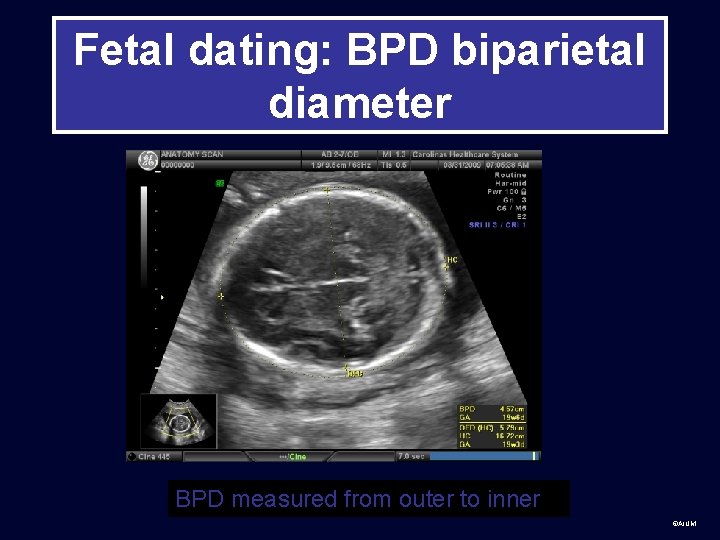

Second Trimester • After 13 -14 weeks, measurements used for dating are: biparietal diameter (BPD), head circumference (HC), abdominal circumference (AC), and femur length (FL) ©AIUM

Fetal dating: BPD biparietal diameter BPD measured from outer to inner ©AIUM